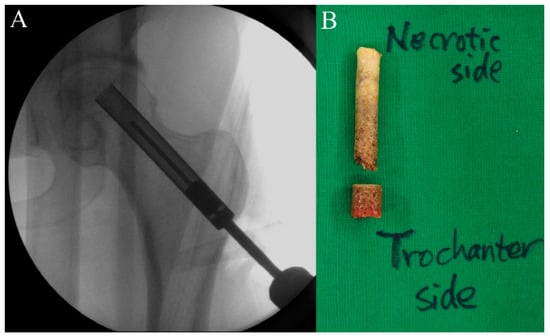

2.5. Procedure